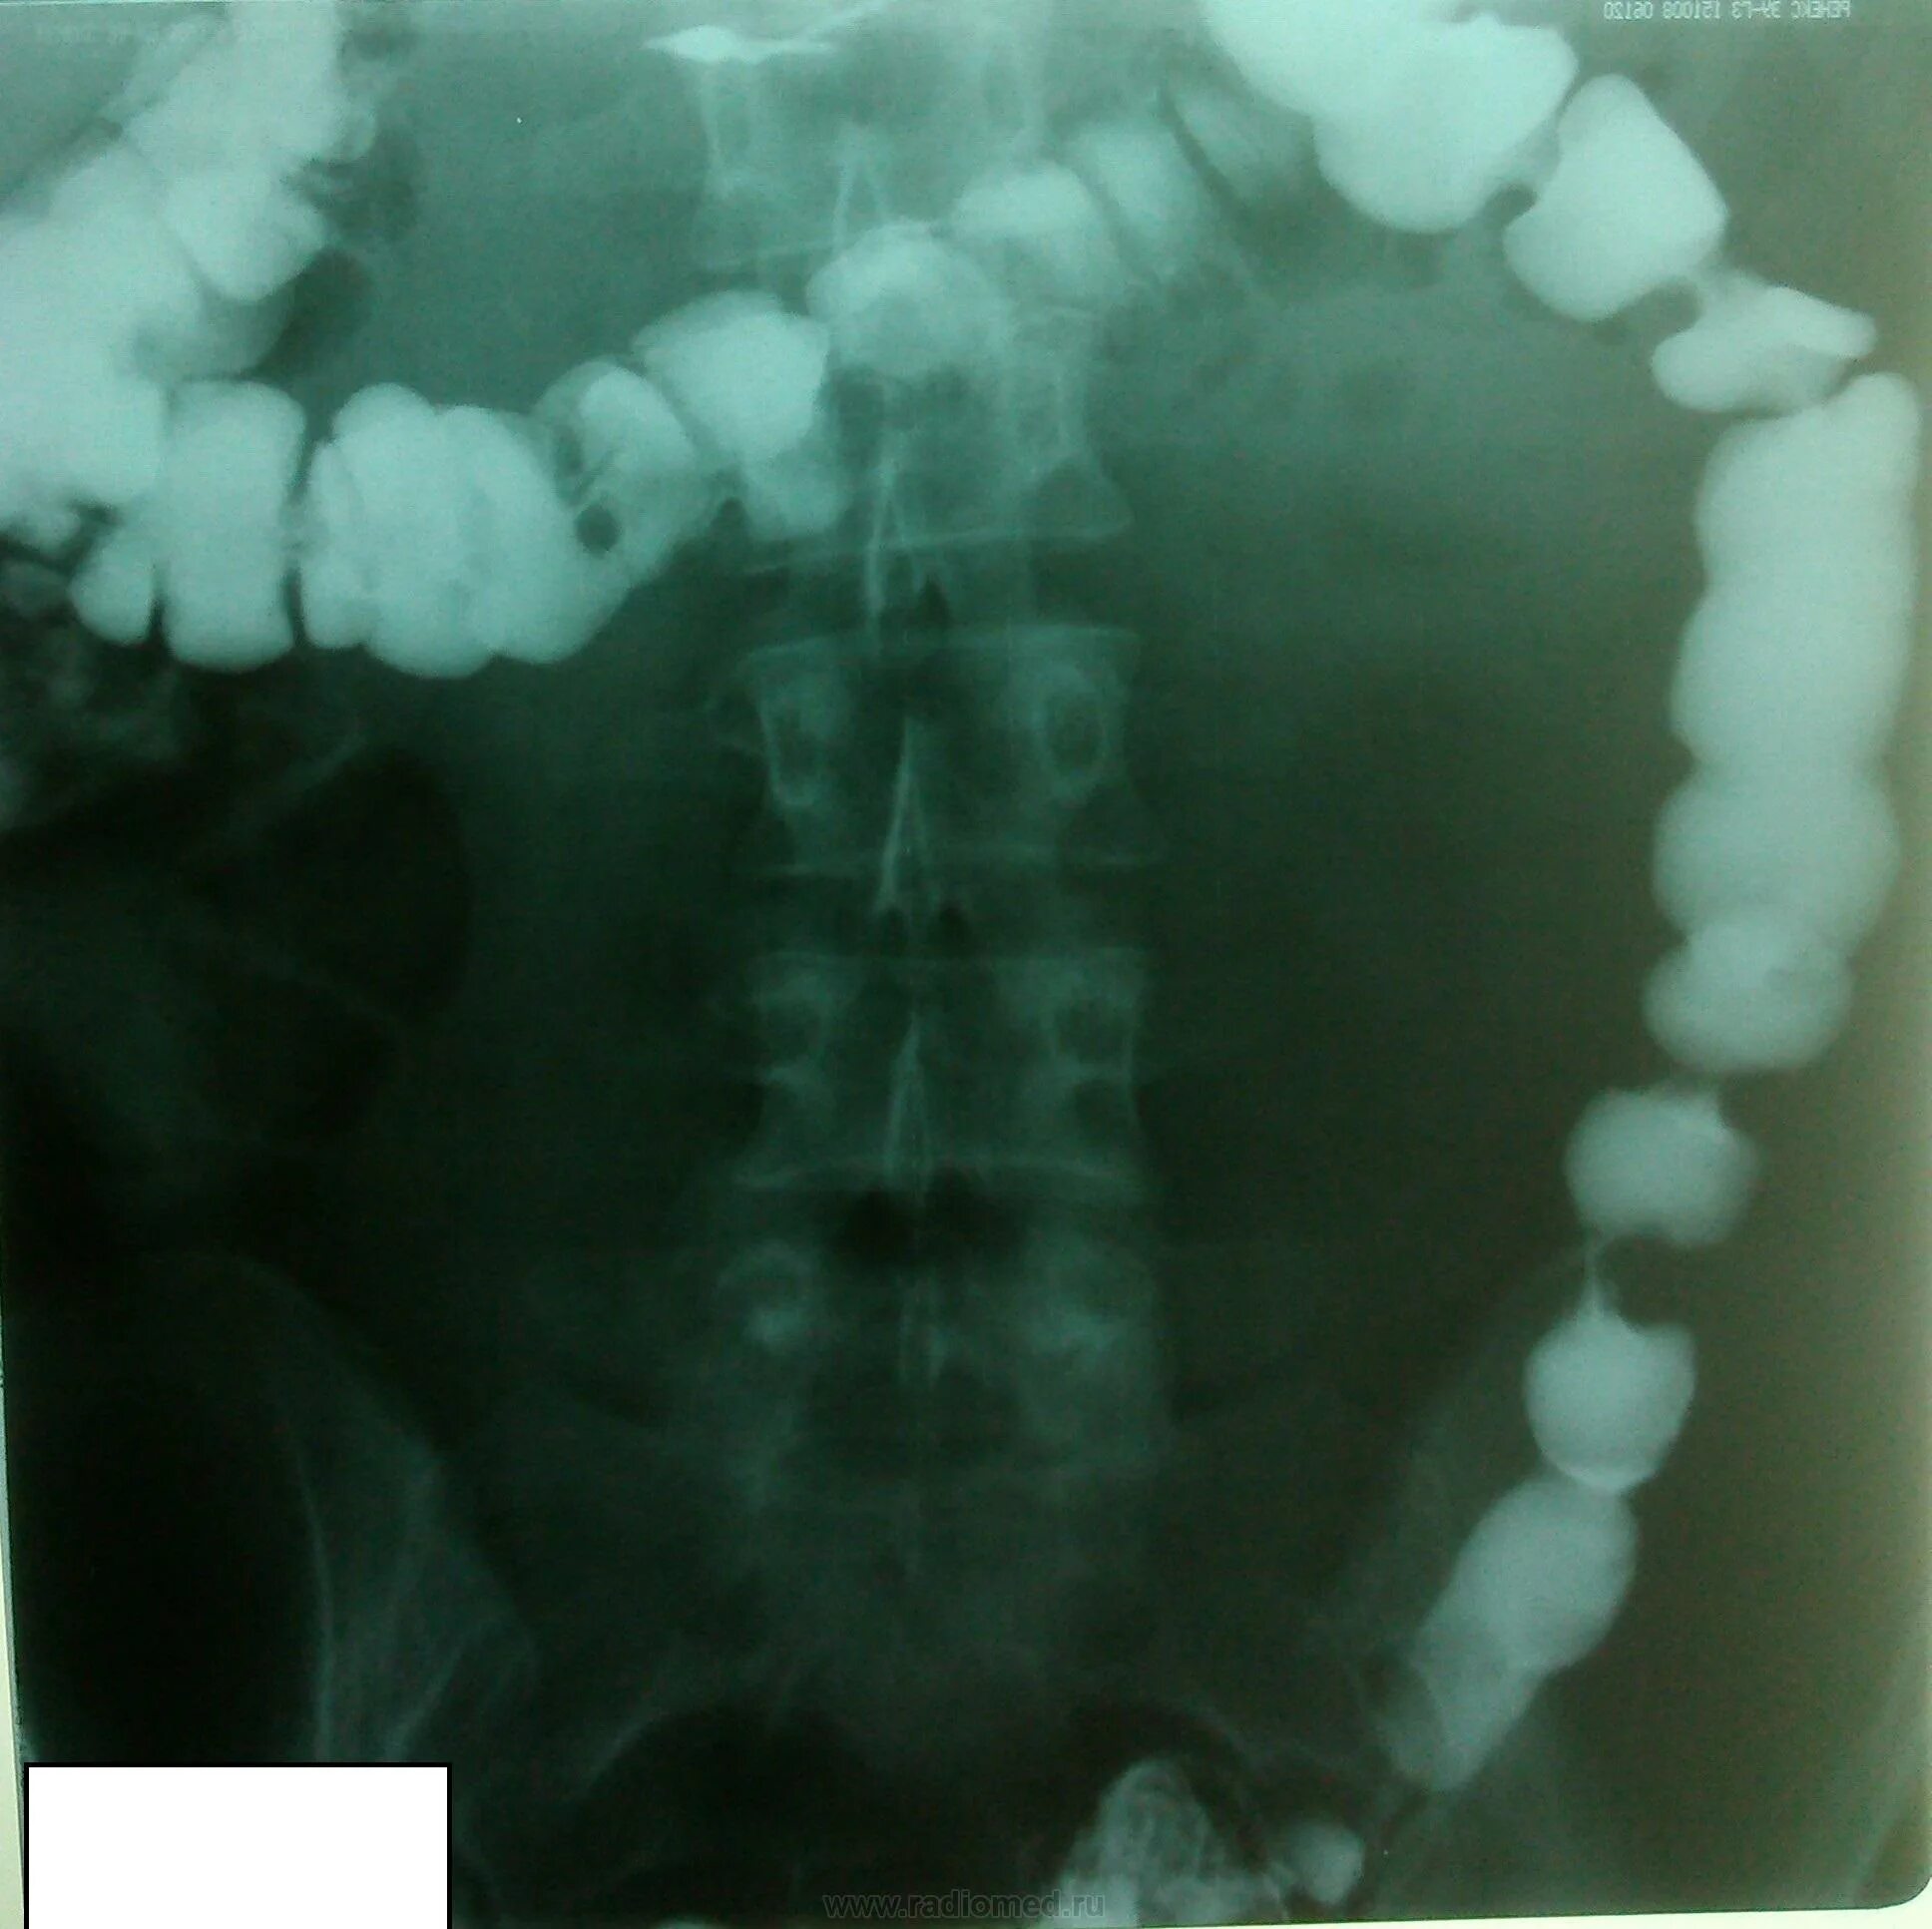

Долихосигма кишечника у ребенка